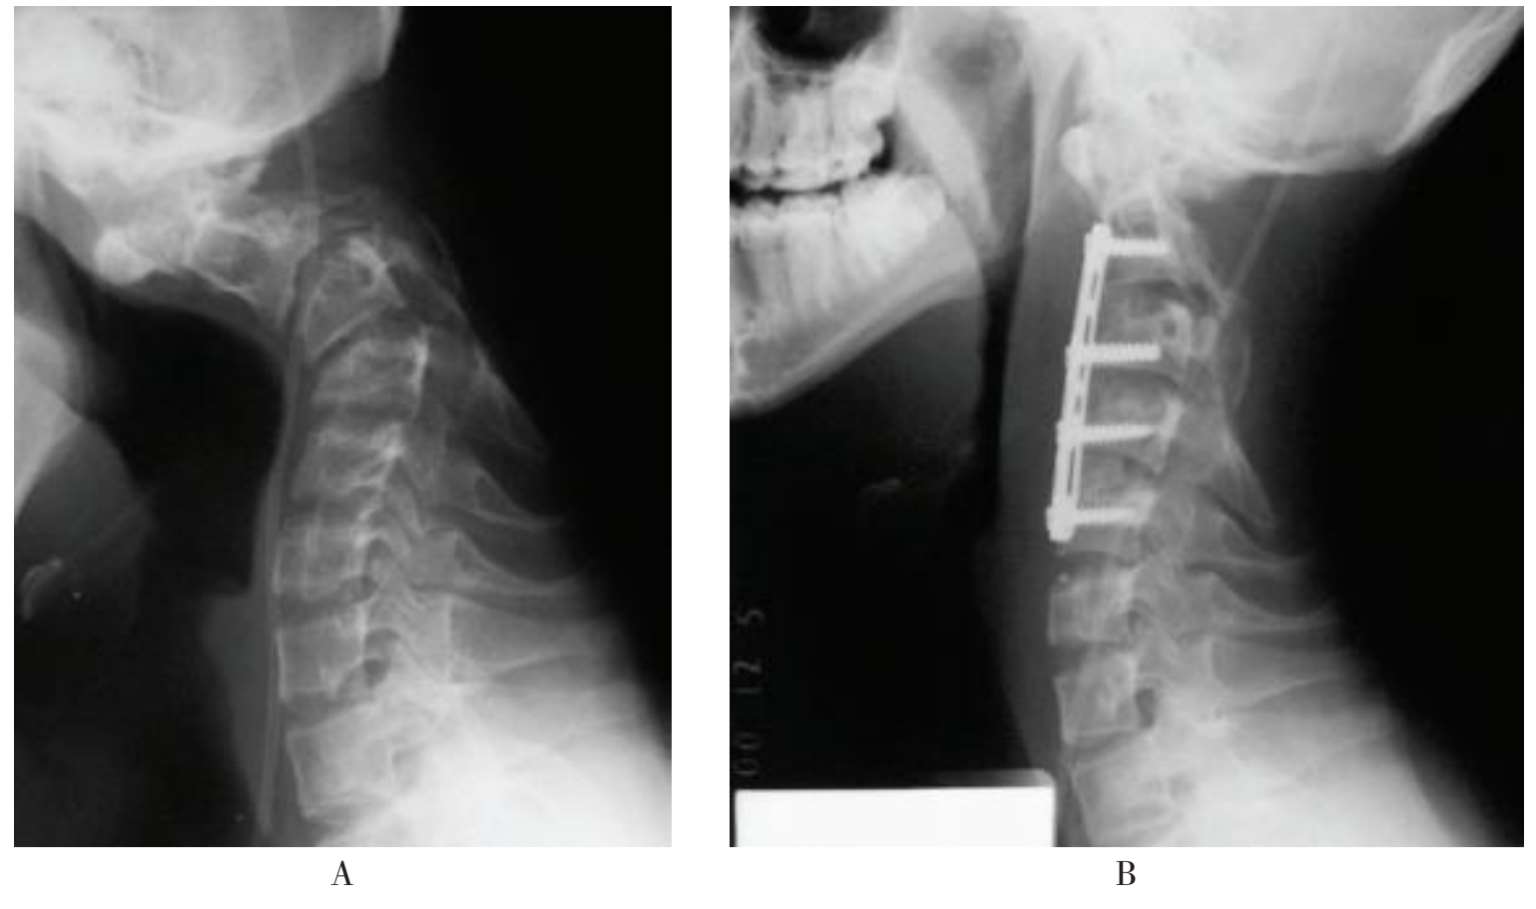

(1)例1:男性,14岁,1年半前因颈椎椎管内肿瘤行C 2 、C 3 椎板切除,椎管内肿瘤切除术,术后逐渐出现颈椎后凸畸形,合并慢性颈脊髓病(图1-50A)。入院后先行颅骨牵引2周后,颈椎后凸畸形获得大部分矫正,再行颈前路2~5椎间盘切除、多平面椎间撑开后凸畸形矫正术,术后畸形基本矫正,脊髓功能改善(图1-50B)。

A.术前;B.术后

图1-50 颈椎后凸畸形合并慢性颈脊髓病,先行颅骨牵引2周后,再行颈前路2~5椎间盘切除、多平面椎间撑开后凸畸形矫正术,手术前后对照